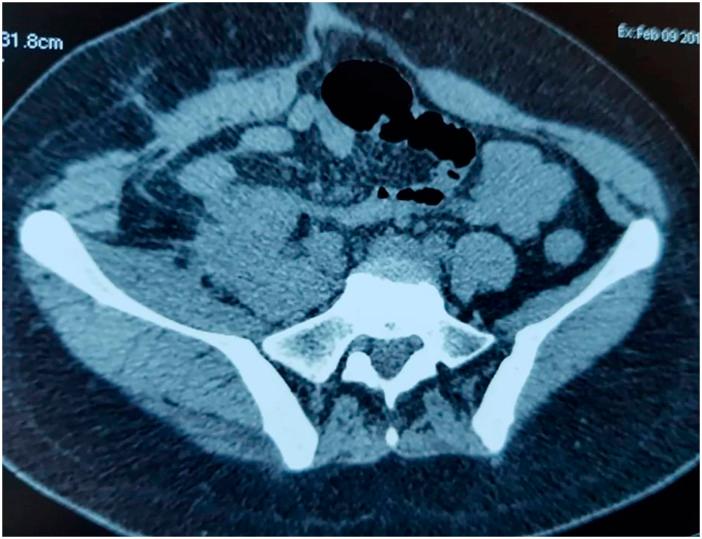

We report the case of a 23-year-old girl, with learning disability, operated in emergency for acute peritonitis. Peroperatively, we discovered a peritonitis secondary to a bulky perforated cecal tumor. We performed a right colectomy and an ileostomy. The posterior margin of the resection was macroscopically involved. The diagnosis of colonic schwannoma was confirmed with immunopathological examination of the surgical specimen. Surgical exploration 4 months later and morphological investigations during 2 years showed stability of the tumoral residue in the right iliac fossa. However, we noticed, on CT scanning control 2 years postoperatively, the appearance of a mesenteric recurrence. Exploratory laparotomy confirmed the unresectability of this mesenteric mass and showed the presence of multiple parietal nodules whose biopsies revealed their neurofibromatous nature. The 4 year follow-up of the patient didn't reveal any complication rather than need to right nephrostomy due to ureter compression by the primary tumoral residue.

我们报告一名23岁有学习障碍的女孩的病例,她因急性腹膜炎接受急诊手术。术中,我们发现腹膜炎继发于一个巨大的穿孔性盲肠肿瘤。我们进行了右半结肠切除术和回肠造口术。切除的后缘肉眼可见受累。手术标本的免疫病理检查证实了结肠施万细胞瘤的诊断。4个月后的手术探查以及2年的形态学检查显示右髂窝肿瘤残余稳定。然而,我们在术后2年的CT扫描复查中注意到肠系膜复发。剖腹探查证实该肠系膜肿块无法切除,并显示存在多个壁层结节,其活检显示为神经纤维瘤性质。对该患者的4年随访未发现任何并发症,仅因原发性肿瘤残余压迫输尿管而需要进行右肾造瘘。